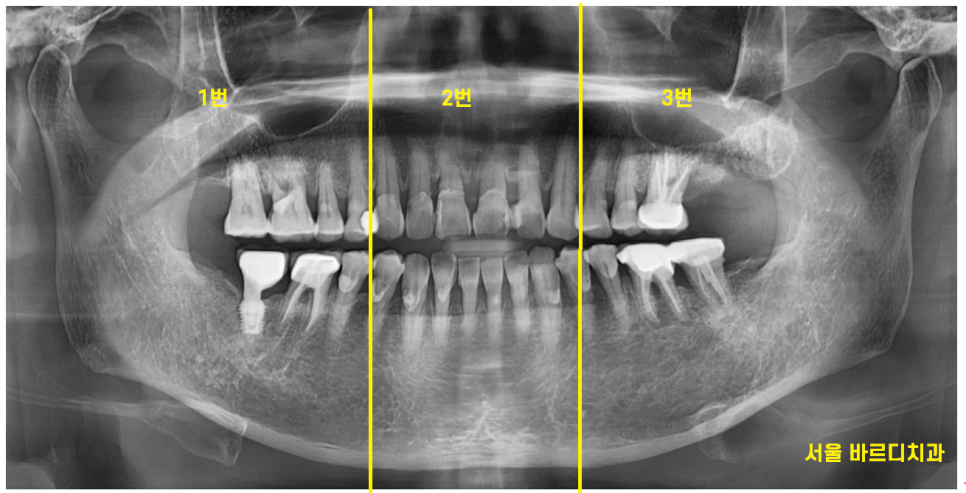

그중에서도 왼쪽 맨 끝에 치아가 심각했습니다.

뿌리를 감싸고 있는 뼈가

까맣게 보이네요~

염증으로 많이 녹기도 하였고

어금니 흔들림을 동반한 통증

느끼실만큼 많이 상하였습니다.

심각한 왼쪽 맨 위 치아 1개를 발치하고

어금니 흔들림 최소화 하기 위하여

나머지 치아들은 잇몸치료 하면서

써보기로 하였습니다.